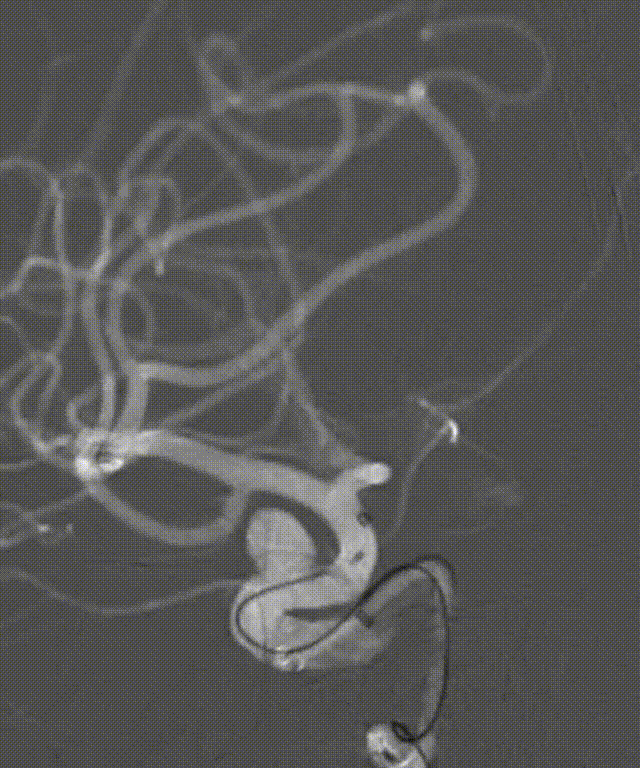

术前DSA造影:动脉瘤大小:4.9mm*4.8mm,动脉瘤颈:4.0mm;载瘤动脉远端直径:2.4mm,近端直径:4.0mm,长度:19.9mm。

DSA正位造影

动脉长鞘怎么置入深谋远路 | 千人皆翘首,万唤今始来——国内首款7F长鞘在血流导向密网支架联合弹簧圈栓塞治疗动脉瘤的首次应用_https://www.jmylbn.com_新闻资讯_第21张

DSA侧位造影

动脉瘤大小测量

载瘤动脉测量